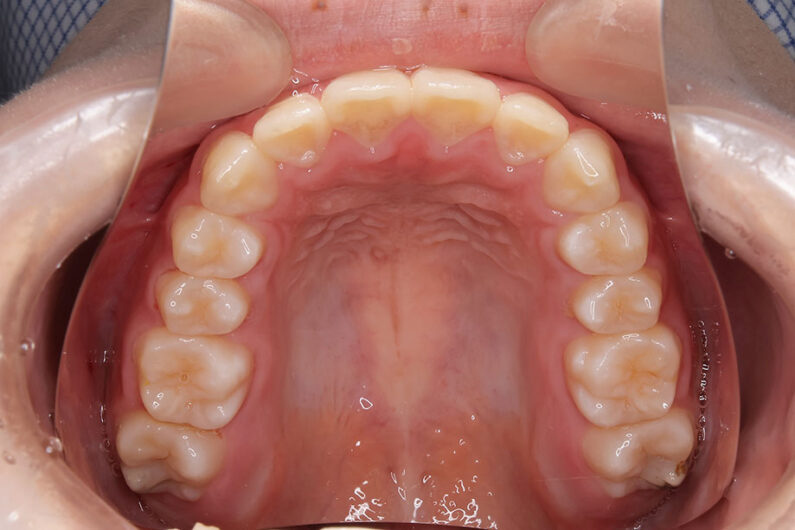

側方歯(犬歯、小臼歯)の生え変わりの時期。 前歯のがたつきを気にされ、小児矯正からの治療を希望されました。 お母様は、矯正治療経験済みですので、治療には前向きで早期治療の必要性を納得されていました。 小児矯正では、永久歯の生え変わるためのスペースを増加させ、がたつきを軽減させることを目的で行います。 残ったがたつきは、全ての永久歯が生え変わってから、本格矯正(マルチブラケット装置での治療)で改善しています。 比較的、叢生量は少ないため、本格矯正は非抜歯にて配列しました。

マルチブラケット 動的治療期間 2年6か月 調整回数16回 特に問題もなく、保定後も安定しています。